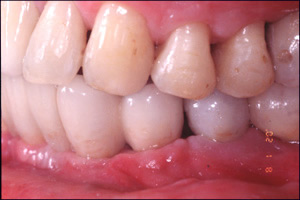

CASE4: 外傷による損傷の症例 主訴:打撲により、水平垂直に骨が欠損した状態をインプラントと骨移植により回復した。